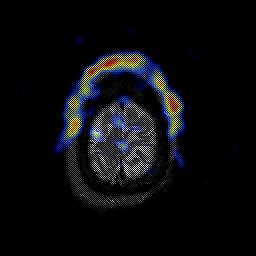

Glioblastoma multiforme overlay -- Slice #47

[Home][Help][Clinical][Tour 1][Tour 2][Tour 3] Slice 47